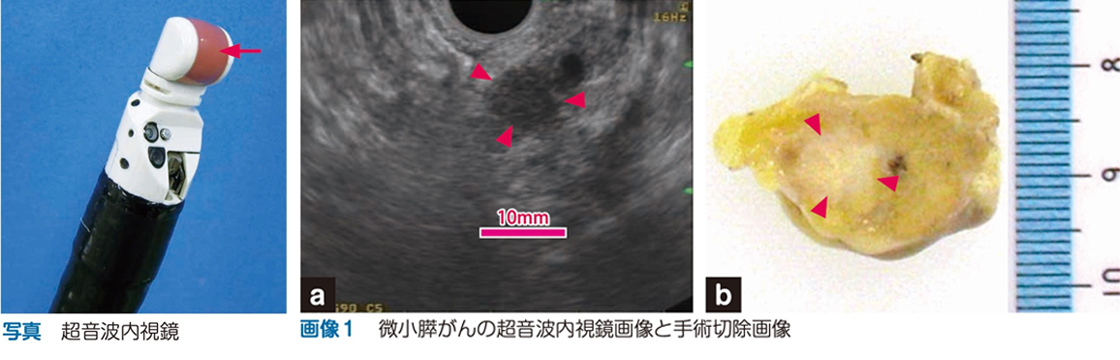

この検査としては、超音波内視鏡、CT、MRIがあります。特に超音波内視鏡検査(写真)は、内視鏡の先端部に小型のエコー装置が取り付けられ、消化管の近くにある膵臓を近距離から観察する方法です。最も高感度で膵がん(画像1)を検出することができ、この検査を定期的に行った場合、手術可能な状態で発見される可能性が高いことを当院が発表しています。

(写真)内視鏡の先端部に小型エコー()を取り付けています

(画像1)a.超音波内視鏡像。膵体部に直径9mmのがん()を認めます

b.手術で取り除いた膵がん。超音波内視鏡と同様に直径9mmの膵がん()を認めます